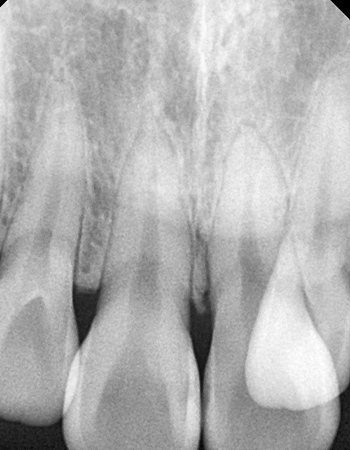

확장 전

확장 후

CASE 02